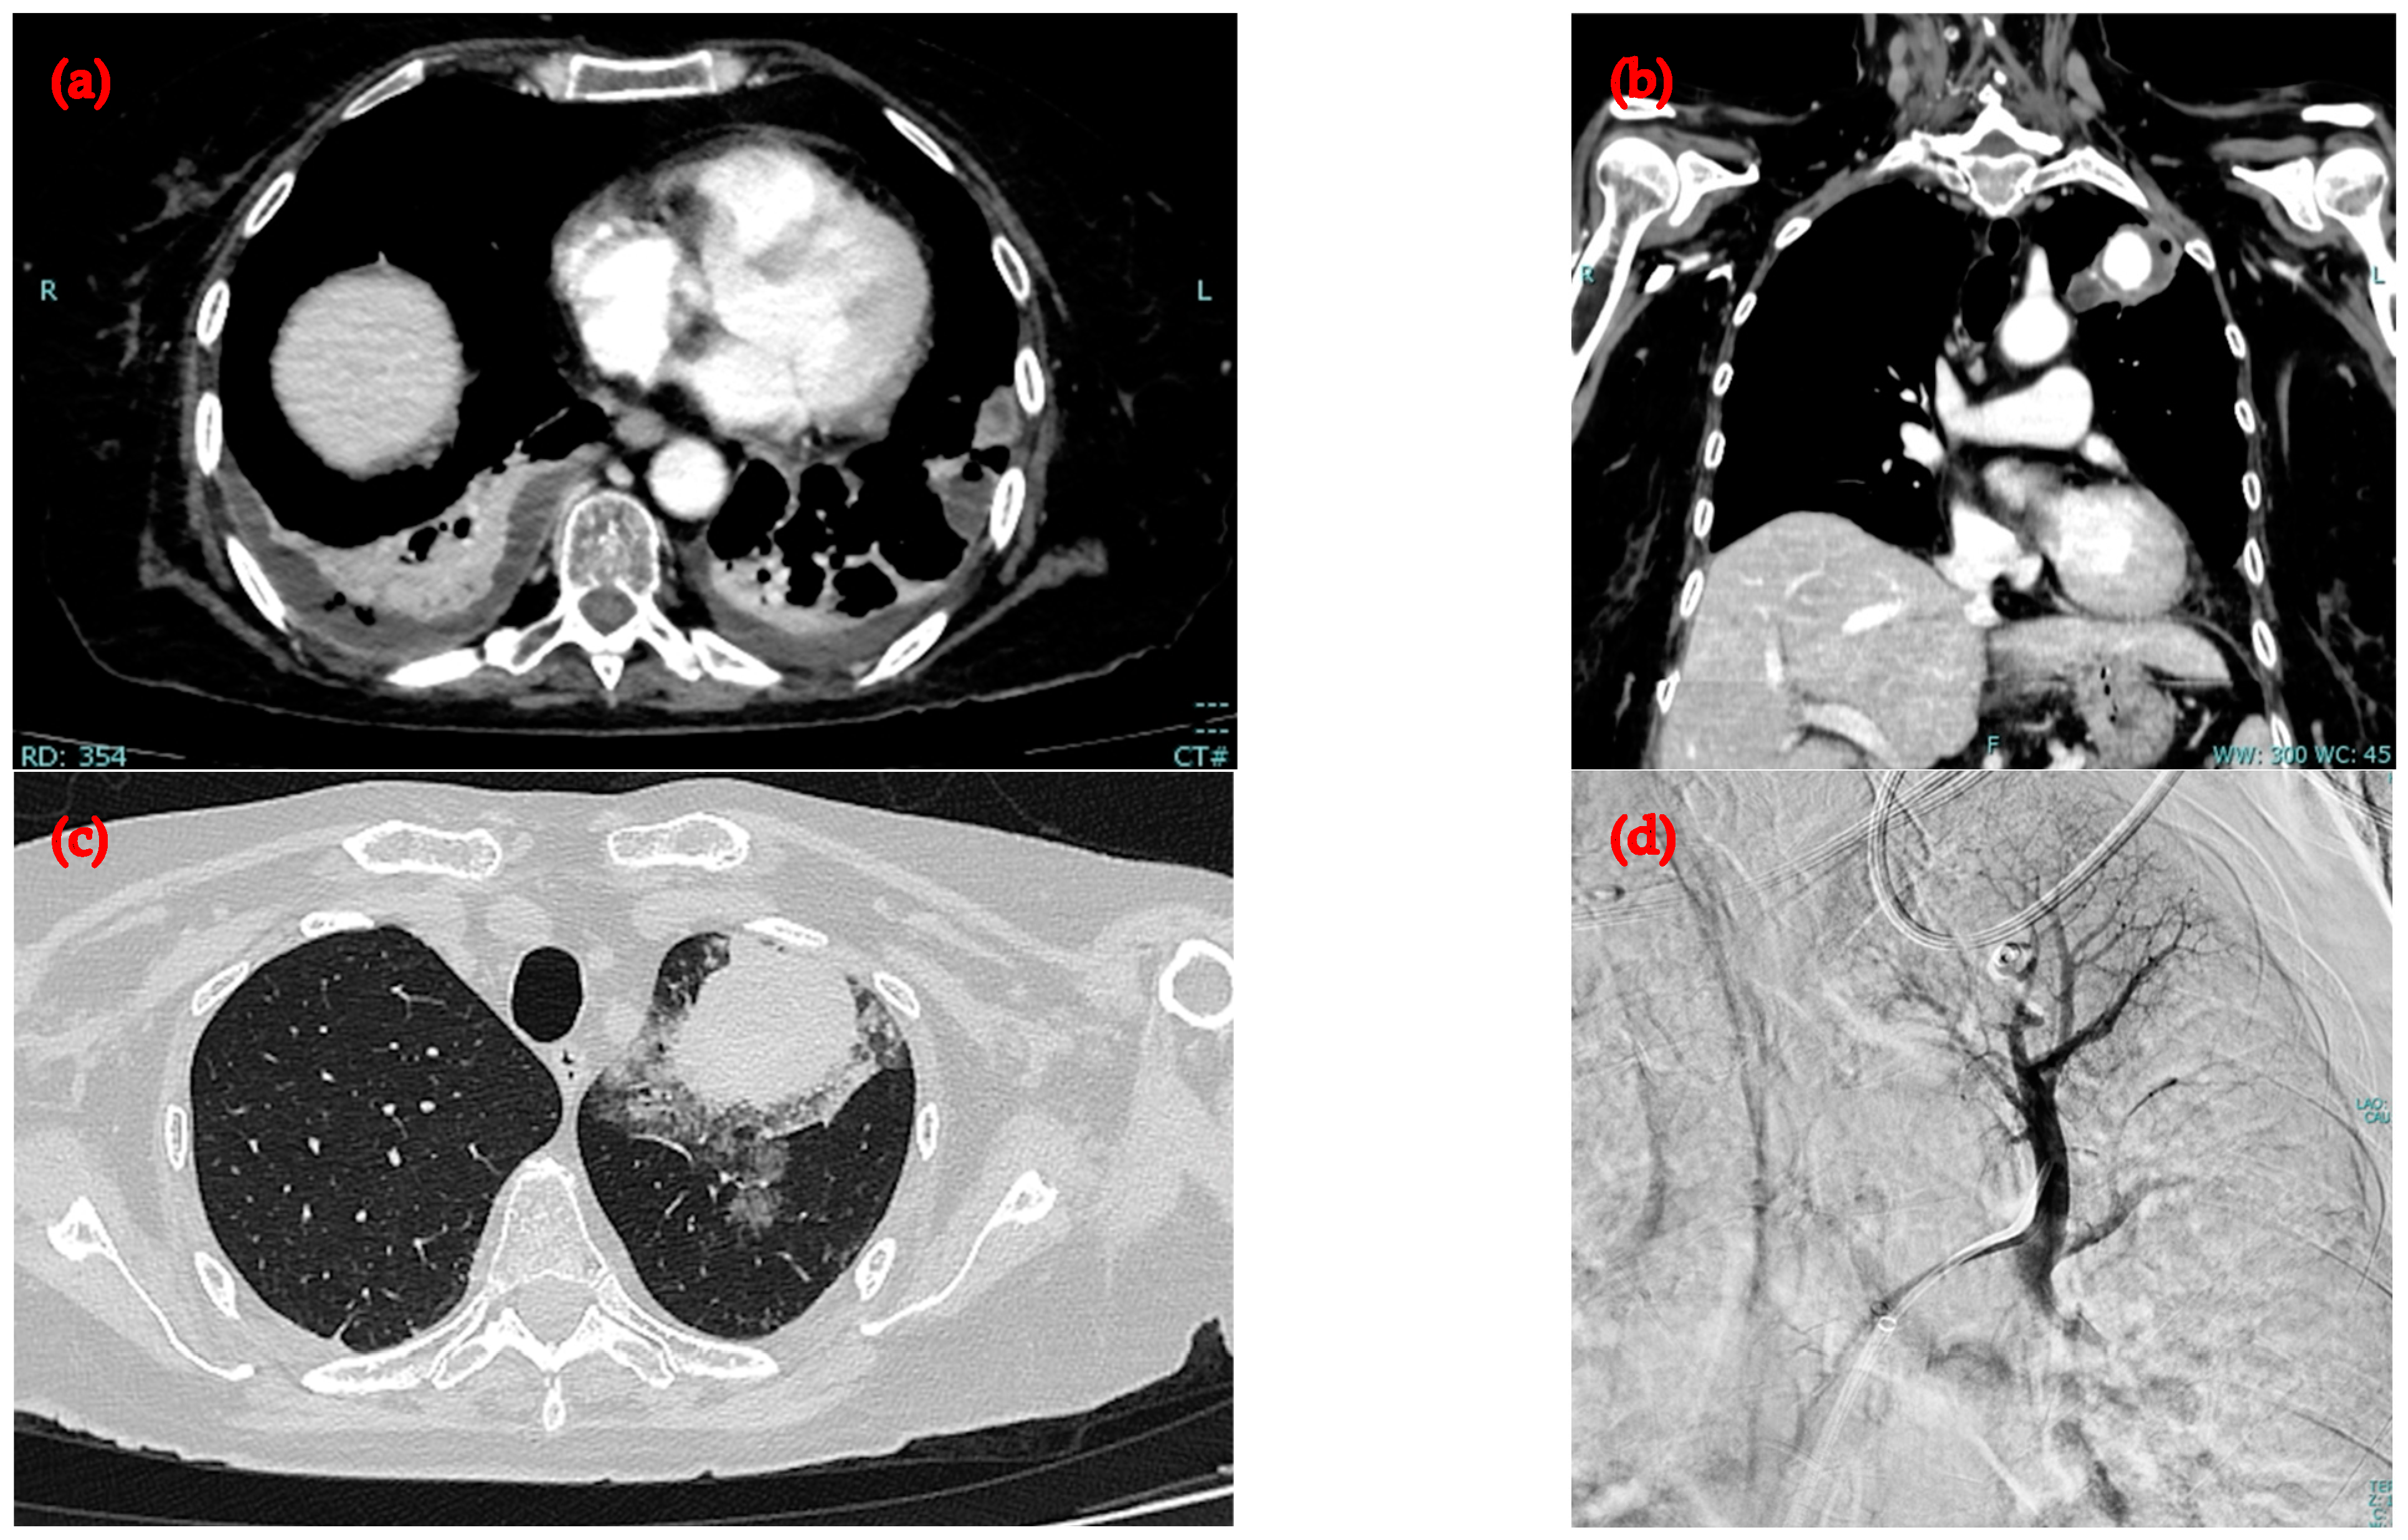

2.2. Second Admission to the Same Hospital

2.3. Admission to the Infectious Diseases Unit of Our University Hospital